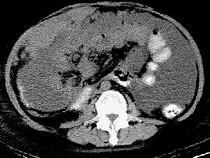

问题 男,51岁,直肠癌术后一年,腹胀,纳差,消瘦,影像检查如图,最可能的诊断是 ( )

选项 A.直肠癌肝转移 B.直肠癌网膜转移 C.肝硬化腹水 D.术后改变 E.肠梗阻

答案 B